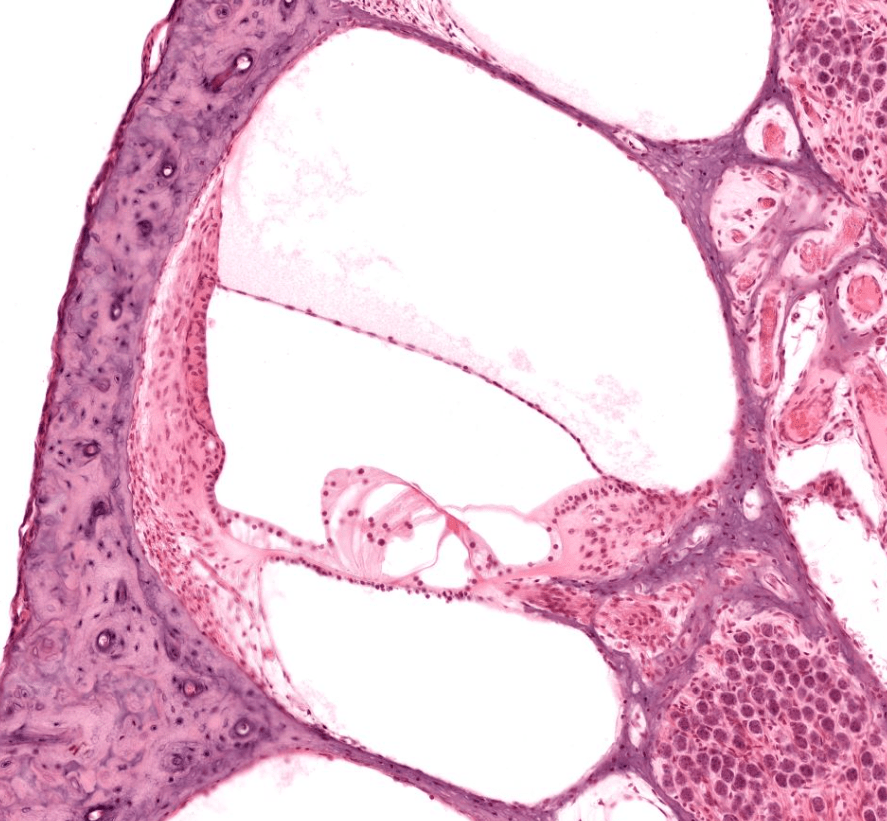

ÓRGANO DE CORTI

Es considerado el epitelio sensitivo de la cóclea, se encarga de procesar los estímulos auditivos.

Órgano de Corti, HyE. Recuperada de la Universidad de Yale.

CONDUCTO COCLEAR

Identifique las rampas y las membranas a lo largo del conducto coclear.